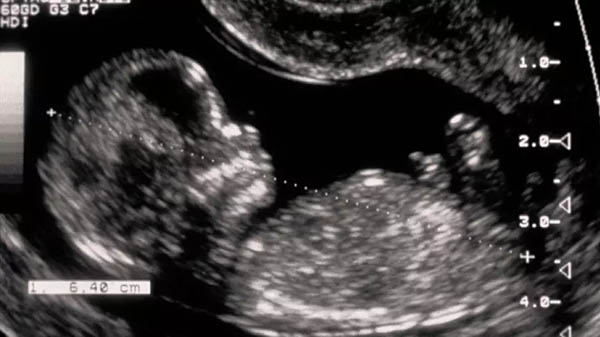

A gyermeknél születésekor Down-szindrómát diagnosztizáltak, bár a szakértők szerint a jelek már az első terhességi ultrahangvizsgálat óta láthatóak lehettek. Ez a kromoszóma-rendellenesség különböző mértékű értelmi és fizikai fogyatékosságot, valamint kapcsolódó egészségügyi problémákat okoz, és egyike azon feltételeknek, amelyek lehetővé teszik a szülők számára, hogy a terhesség orvosi megszakítását kérjék a terhesség teljes időtartamáig.